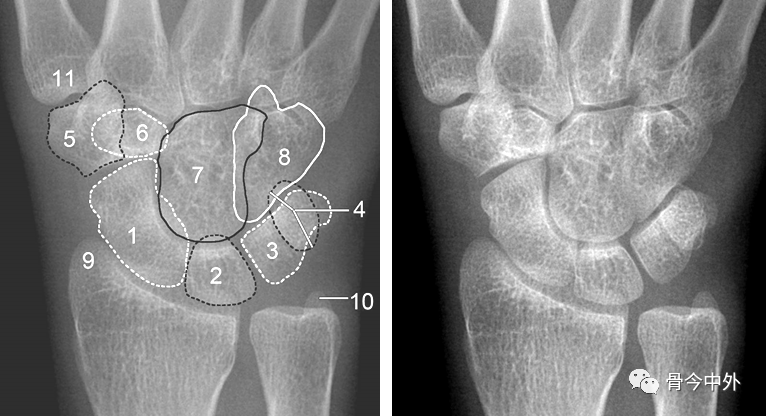

图1 成人期腕关节正侧位及舟骨蝶位片。1.舟骨;2.月骨;3.三角骨;4.豆状骨;5.大多角骨;6.小多角骨;7.头状骨;8.钩骨;9.桡骨茎突;10.尺骨茎突;11.第一掌骨基部。

图2 成人期腕关节正侧位及舟骨蝶位片。1.舟骨;2.月骨;3.三角骨;4.豆状骨;5.大多角骨;6.小多角骨;7.头状骨;8.钩骨;9.桡骨茎突;10.尺骨茎突;11.第一掌骨基部。